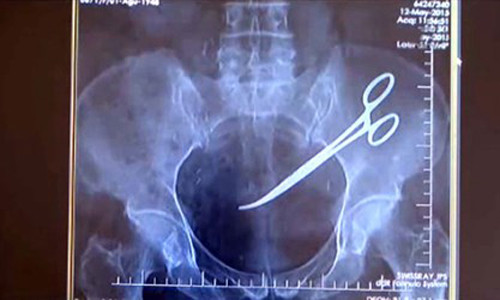

Bà Hanim Ozgul, 67 tuổi người Thổ Nhĩ Kỳ tá hoả khi phát hiện có một chiếc kéo phẫu thuật nằm trong ổ bụng của mình từ sau ca phẫu thuật điều trị ung thư cách đây 5 năm.

Năm năm sau, vào đầu tháng 12/2015, do quá đau ở dạ dày và bụng, bà Hanim quyết định tìm đến một bệnh viện khác để thăm khám. Các bác sỹ tại đây đã không thể tin nổi vào mắt mình khi cầm trên tay hình ảnh chụp X-Quang của bà. Theo đó, toàn bộ phần ổ bụng của bà bị viêm nhiễm nặng do có một "dị vật".